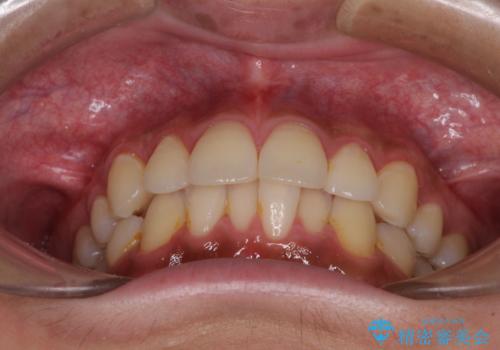

- 矯正治療の後戻りを気にして来院された患者様です。

後戻りは軽微であったので、インビザライン・ライトにより矯正治療を行うこととしました。